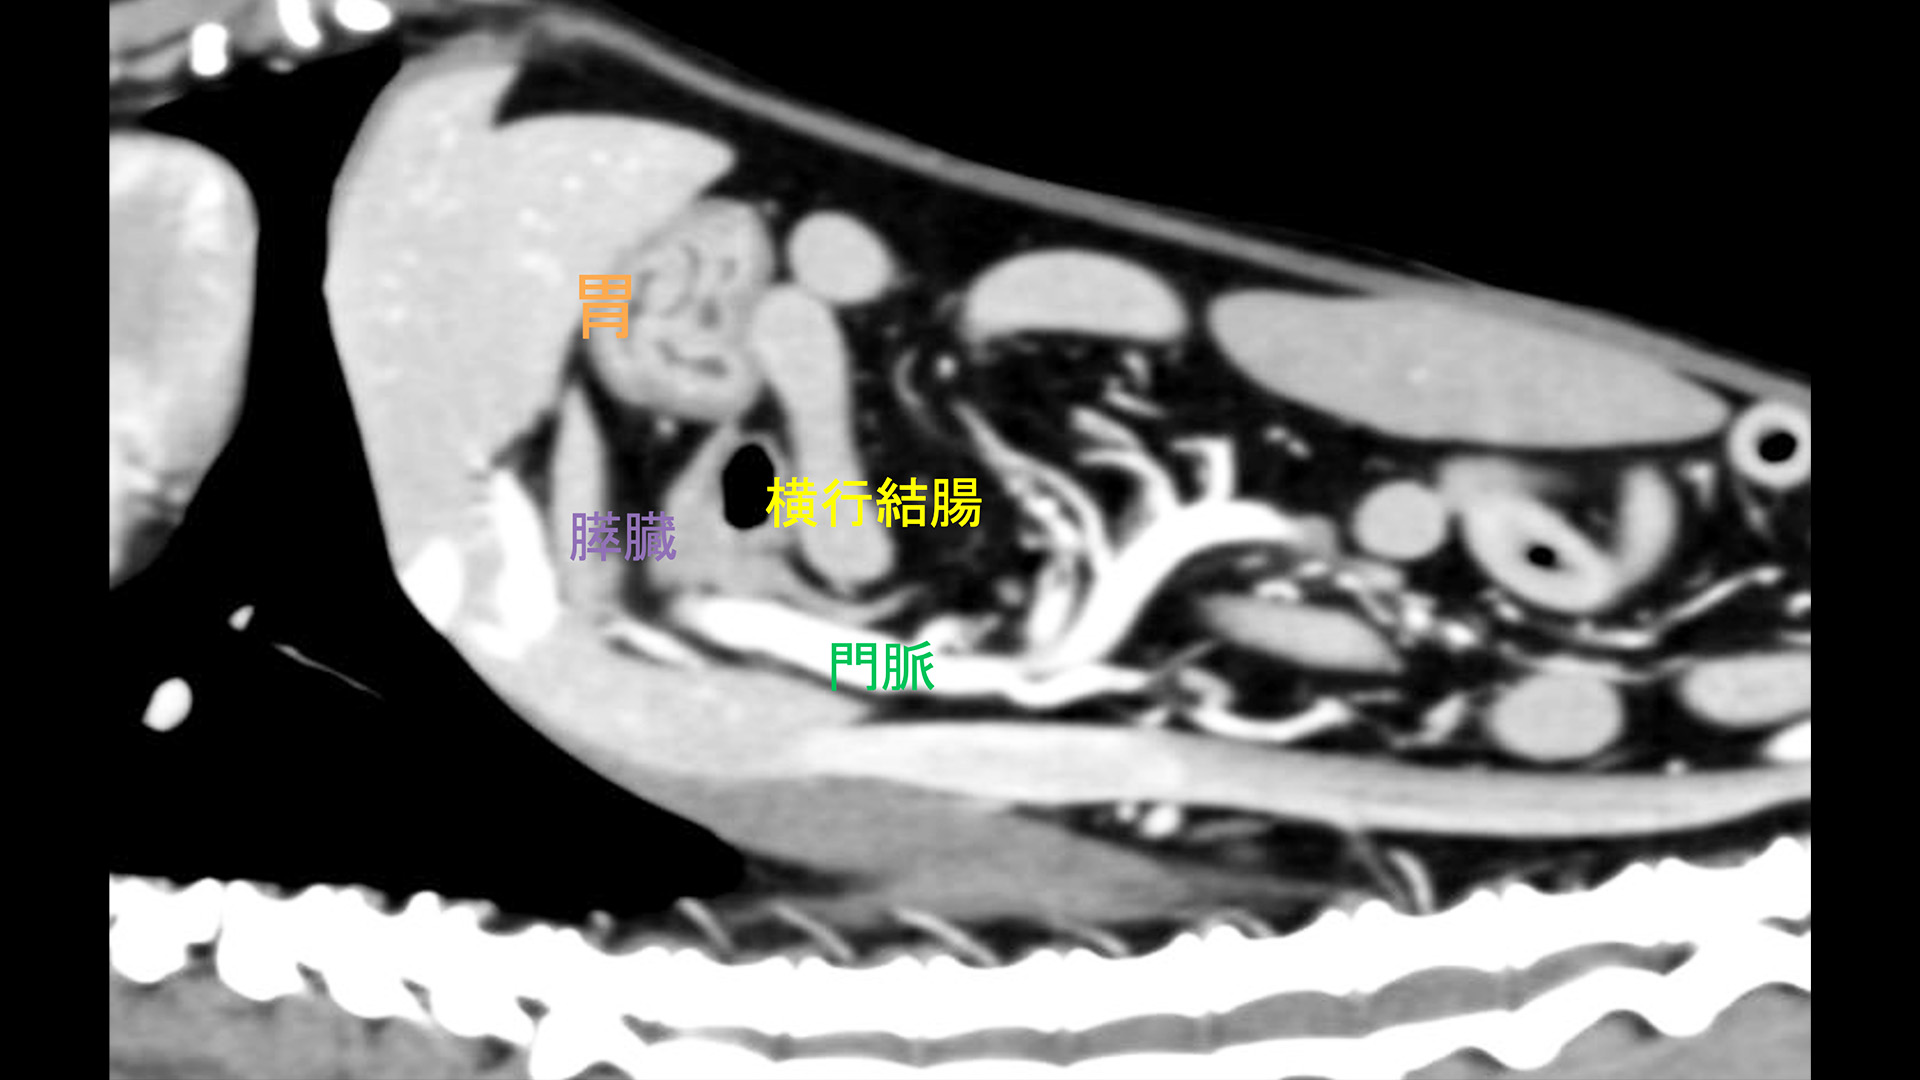

• MRI 、CT、または超音波スキャンで腫瘍の大きさと位置を確認します。